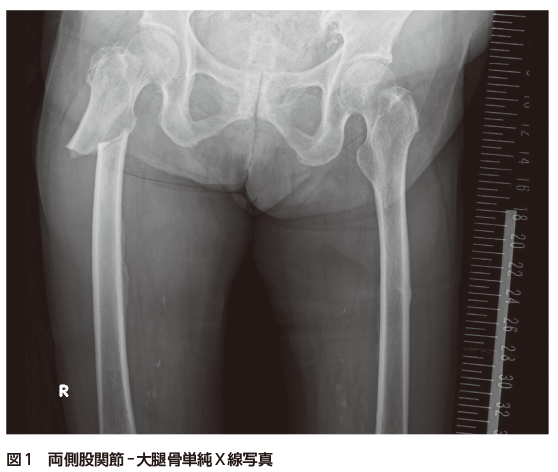

1. Q1:両側股関節-大腿骨単純X線写真(図1),単純CT(図2)の画像所見は?

図2 両側股関節-大腿骨単純CT(冠状断)

A)右大腿骨,B)左大腿骨

誌面掲載画像は,A)赤枠 B)青枠で示す